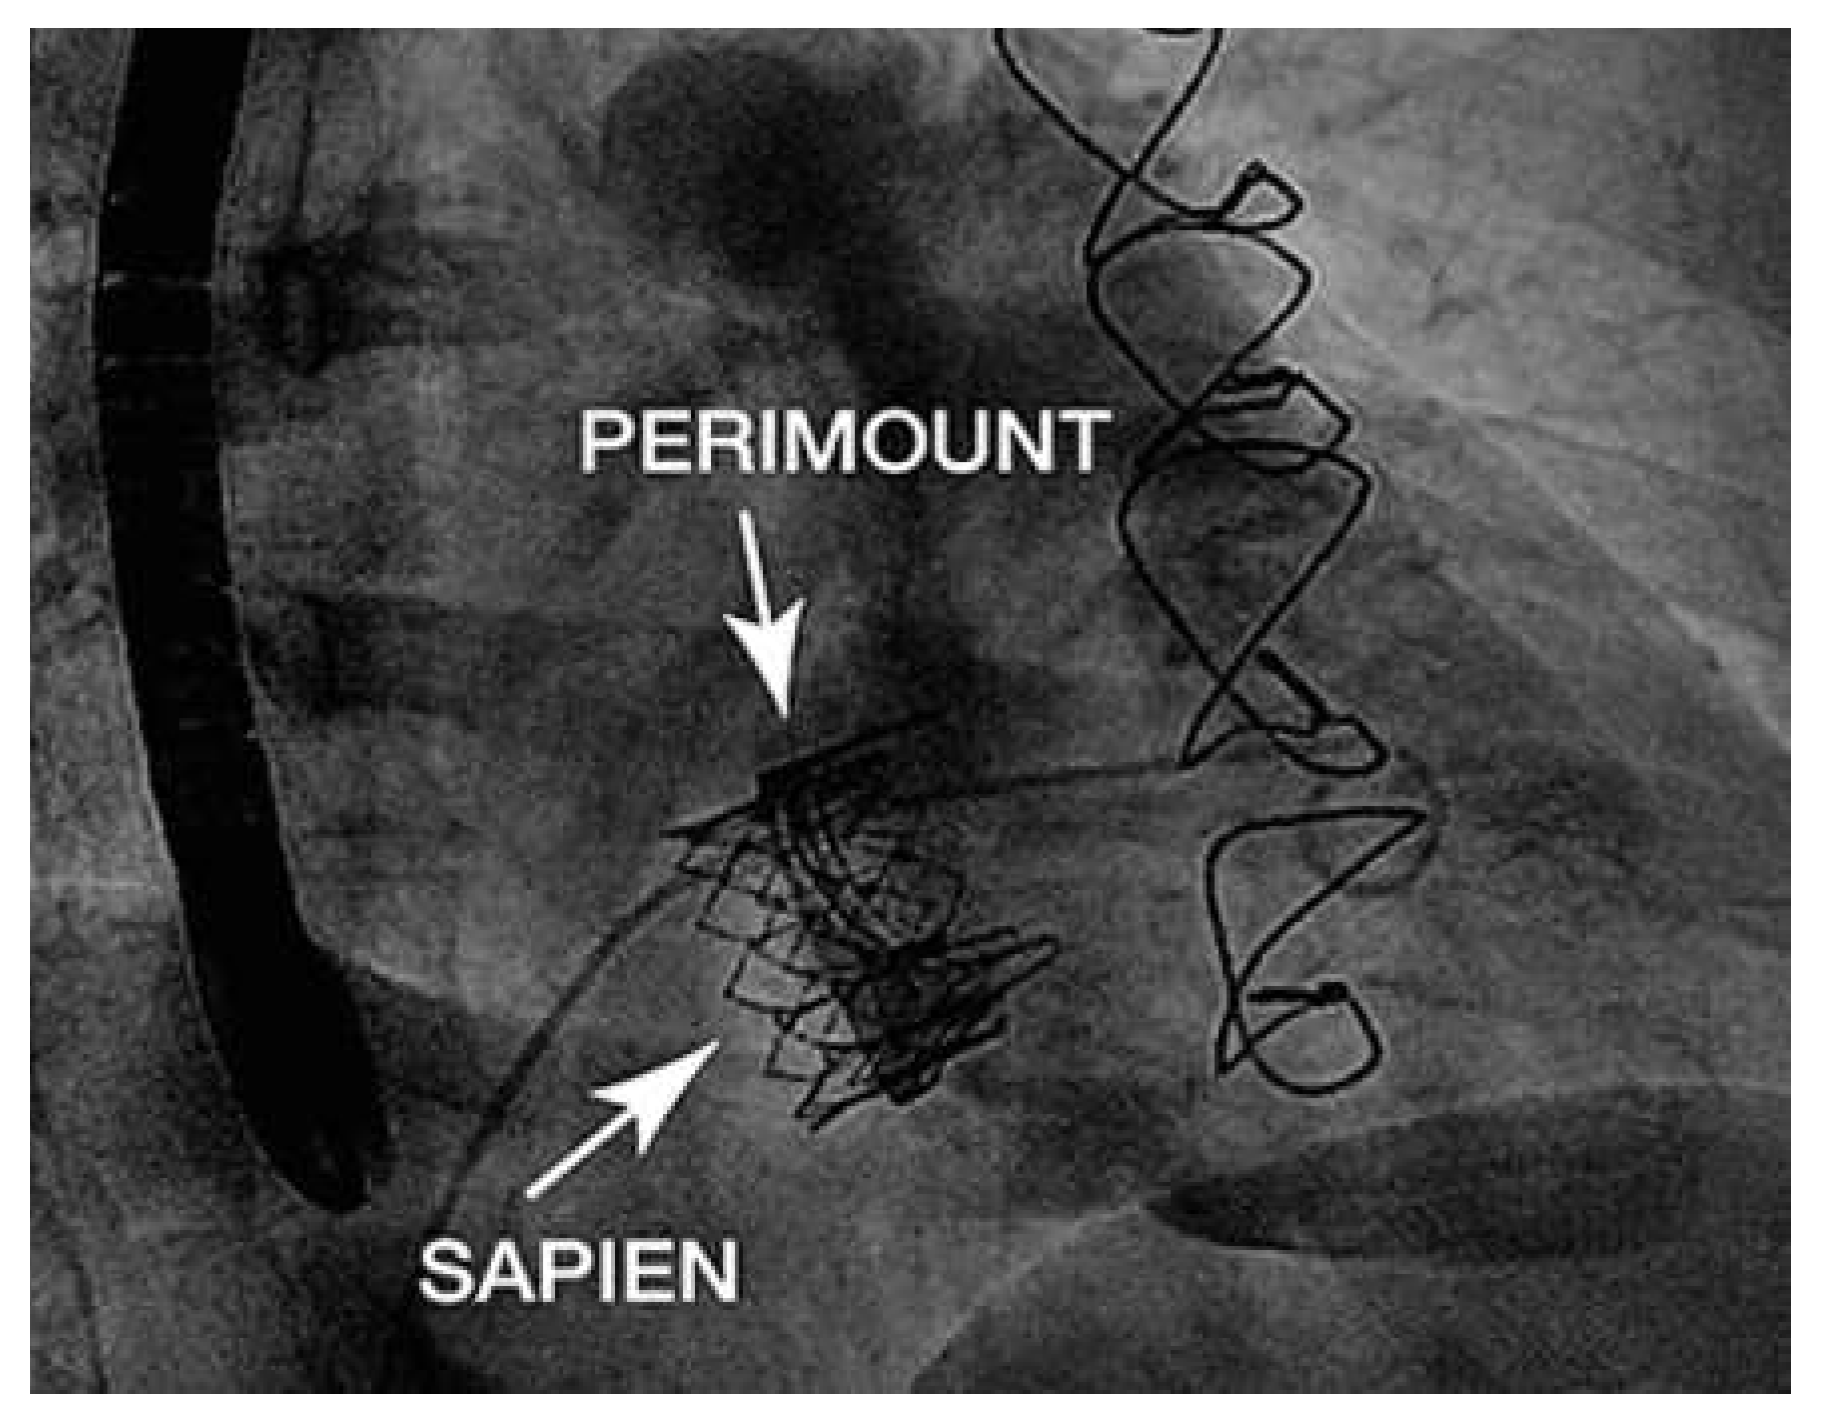

A Valve-in-Valve Approach for Ebstein’s Anomaly

Case report